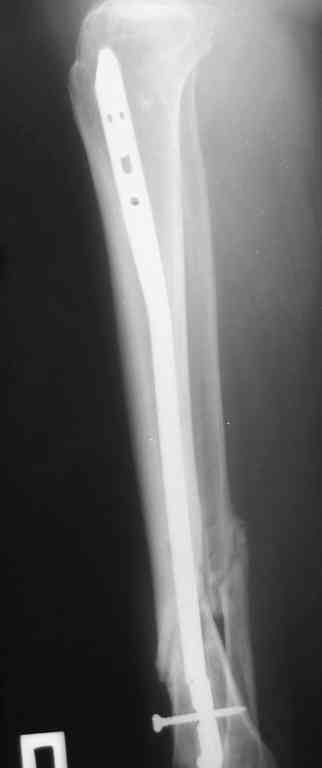

Прилагаются.

Я бы выбрал следующее:

- удаление проксимального куска гвоздя

- остеотомия малоберцовой кости

- внешний остеосинтез в режиме компрессия-дистракция-компрессия.

Да , обсуждалась и оптимальным штифтом был выбран " Мастер" Остеомед 10 мм и винты 5 мм, но увы все наши благие намерения разбились о нашу действительность и материальные возможности больной, обращение ее в страховую компанию и т.д., вообщем выкручивались из внутренних резервов, а они были такими 9 мм штифт Остеомед, под 4 мм винты. Ограничили нагрузку. Ошиблись еще и с оценкой сращения, дали полную нагрузку+ больная поправилась на 18 кг, и вот теперь имеем , что имеем.

Действитльность и возвожности остались прежнее, во внутренних резервах есть 11 мм стержень универсальный ( реконструктивный) "Деост-CHM" много спиц и аппарат + ось конечности и отломок штифта и надежда на Ваши советы.